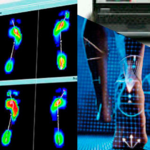

La baropodometría es un estudio que analiza la distribución de las presiones plantares al caminar o estar de pie, utilizando plataformas electrónicas para medir la carga en diferentes zonas del pie. Este análisis ayuda a identificar problemas de pisada, evaluar la necesidad de plantillas ortopédicas y prevenir lesiones